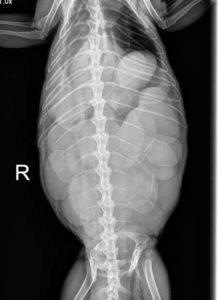

Top view of an X-ray of an iggie with eggs